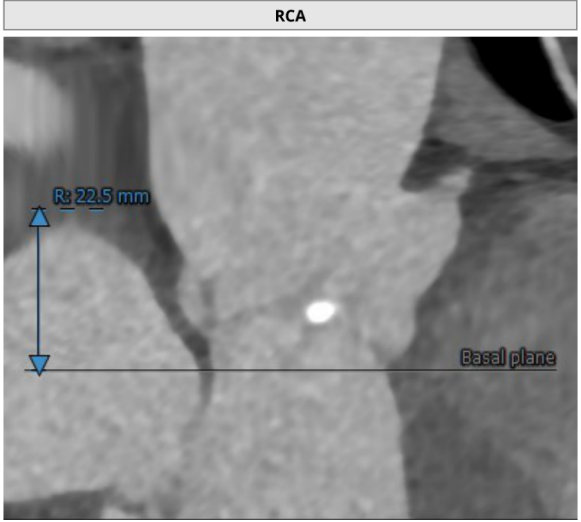

患者主动脉根部、冠状动脉、主动脉增强CT扫描,通过专业评估软件分析提示该患者主动脉瓣为功能型二叶瓣、中度钙化,左右冠窦可见融合、瓦氏窦结构较大,左右冠开口高度尚可,升主动脉最宽处约42.9mm,左室明显扩大。主动脉瓣环平均径约26.3mm,流出道平均径约27.5mm,STJ平均径约34.3mm,双侧股动脉直径均大于6mm。冠脉见钙化灶,钙化积分总和为1590.2;冠脉CTA提示:“左主干、三支冠状动脉粥样硬化改变,局部管腔可见40~60%狭窄”。

右冠高度:22.5mm